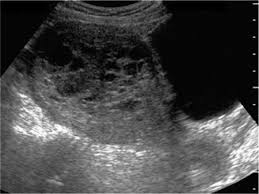

Ultrasound remains the radiological investigation of choice for initial.

The latter four entities are referred to as gestational trophoblastic neoplasia GTN. A common characteristic of all gestational trophoblastic disease is an abnormal proliferation of trophoblast but different components predominate in different tumors. Ultrasound remains the radiological investigation of choice for initial. Gestational trophoblastic neoplasia GTN encompasses a broad spectrum of placental lesions from the pre-malignant hydatidiform mole complete and partial through to the malignant invasive mole choriocarcinoma and rare placental site trophoblastic tumour PSTT. The latter four entities are referred to as gestational trophoblastic neoplasia GTN. There are several histologically distinct types of GTD that range from premalignant complete and partial hydatidiform moles HMs to malignant diseases also known as gestational trophoblastic. Ultrasound in the Diagnosis and Management of GTN Gestational trophoblastic neoplasia GTN includes invasive mole choriocarcinoma PSTT and ETT. Because it is an unusual and serious disease that affects women of reproductive age as well as because its appropriate treatment results in high cure rates it is crucial that radiologists be familiar with gestational trophoblastic disease in order to facilitate its early diagnosis and to ensure appropriate follow-up imaging. Gestational trophoblastic disease GTD is a spectrum of both benign and malignant gestational tumors including hydatidiform mole complete and partial invasive mole Choriocarcinoma placental site trophoblastic tumor and epithelioid trophoblastic tumor.